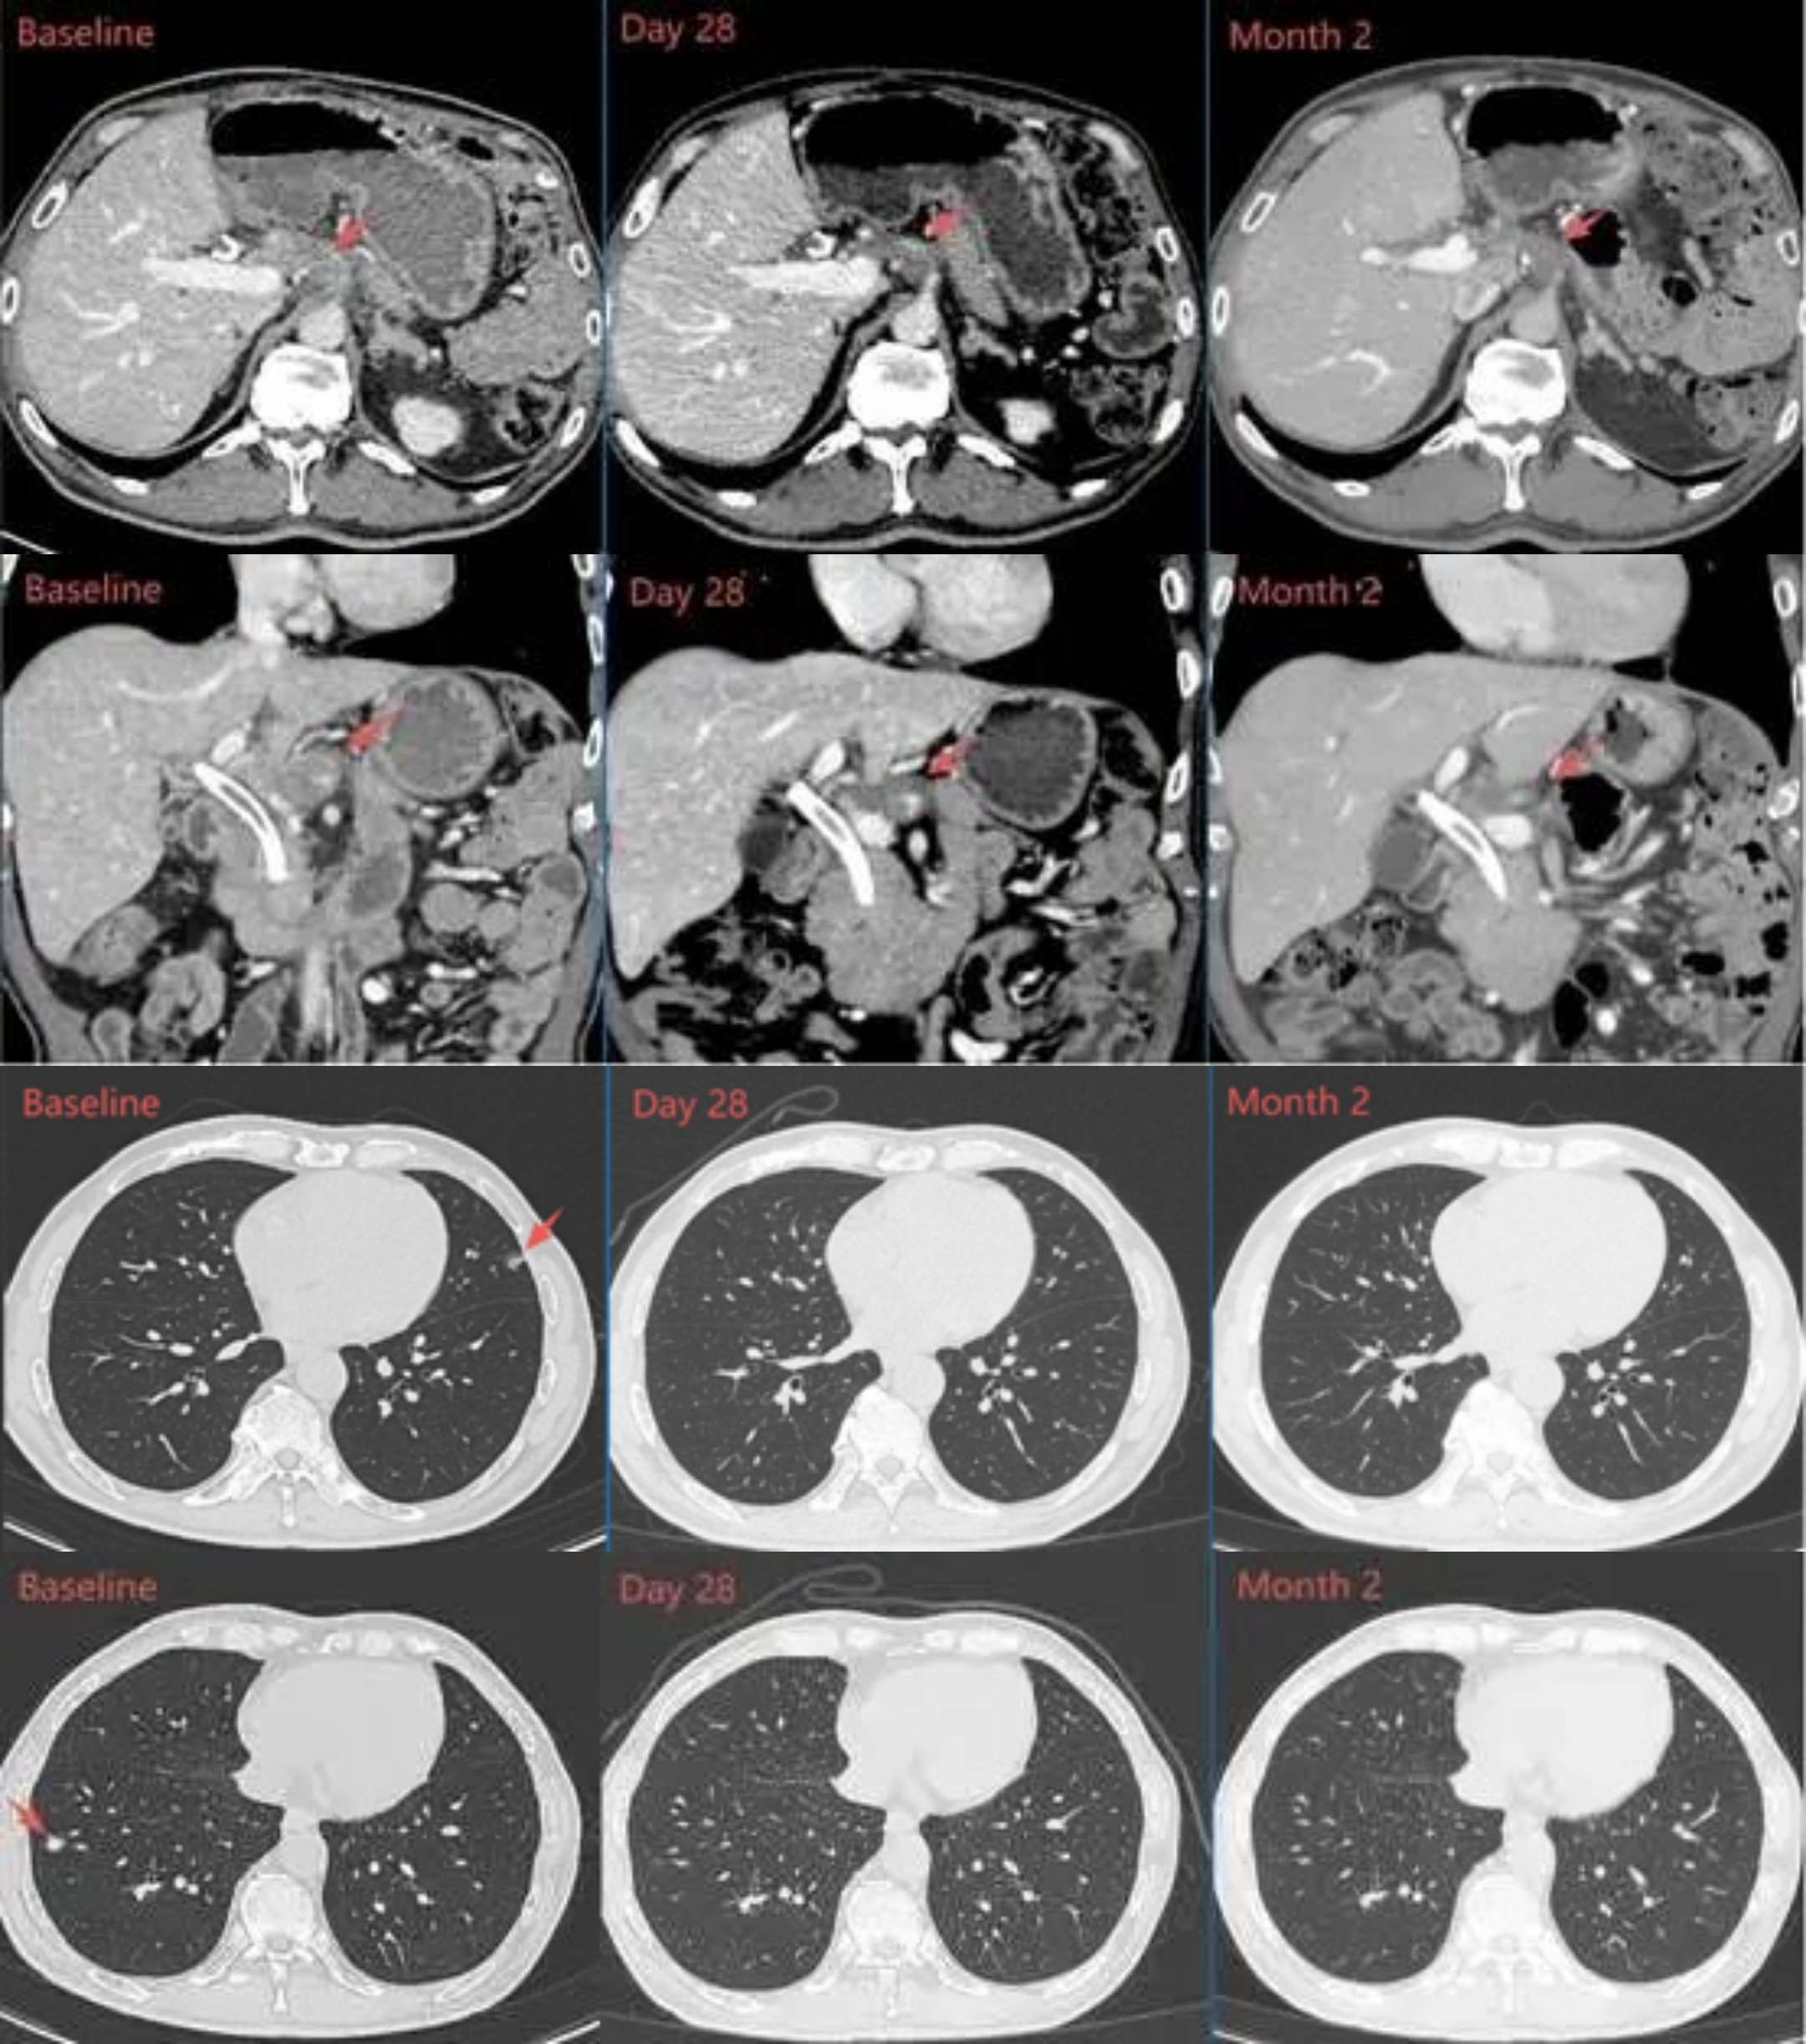

近日,贝莫苏拜单抗联合安罗替尼术后辅助治疗伴高复发风险的肝细胞癌的Ⅱ期临床研究结果发表于《Nature》子刊《Nature Communications》。